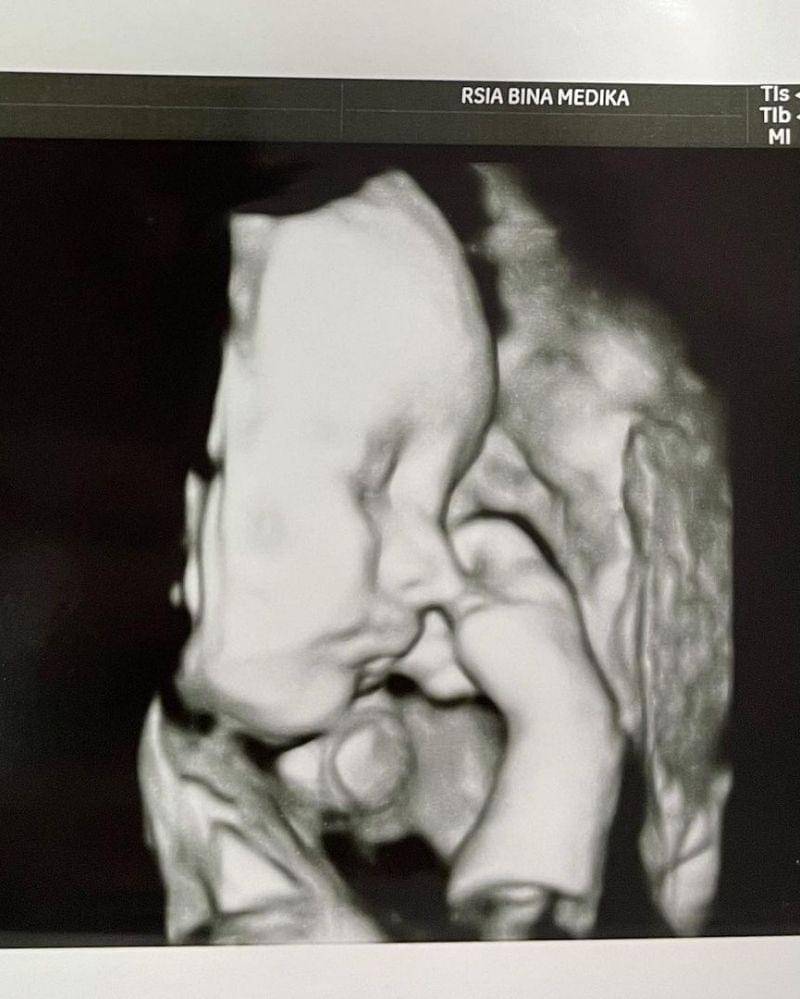

12. Gala Sky Ardiansyah, anak Vanessa Angel dan Bibi Ardiansyah

Siapa yang tak kenal Gala Sky Ardiansyah? Putra pasangan mendiang Bibi Ardiansyah dan Vanessa Angel ini kini tumbuh menjadi anak kesayangan aunty dan uncle online.

Saat masih di dalam kandungan sang mama, Gala Sky sempat menunjukkan pose sedang mengisap jempolnya nih, Ma. Gemasnya!